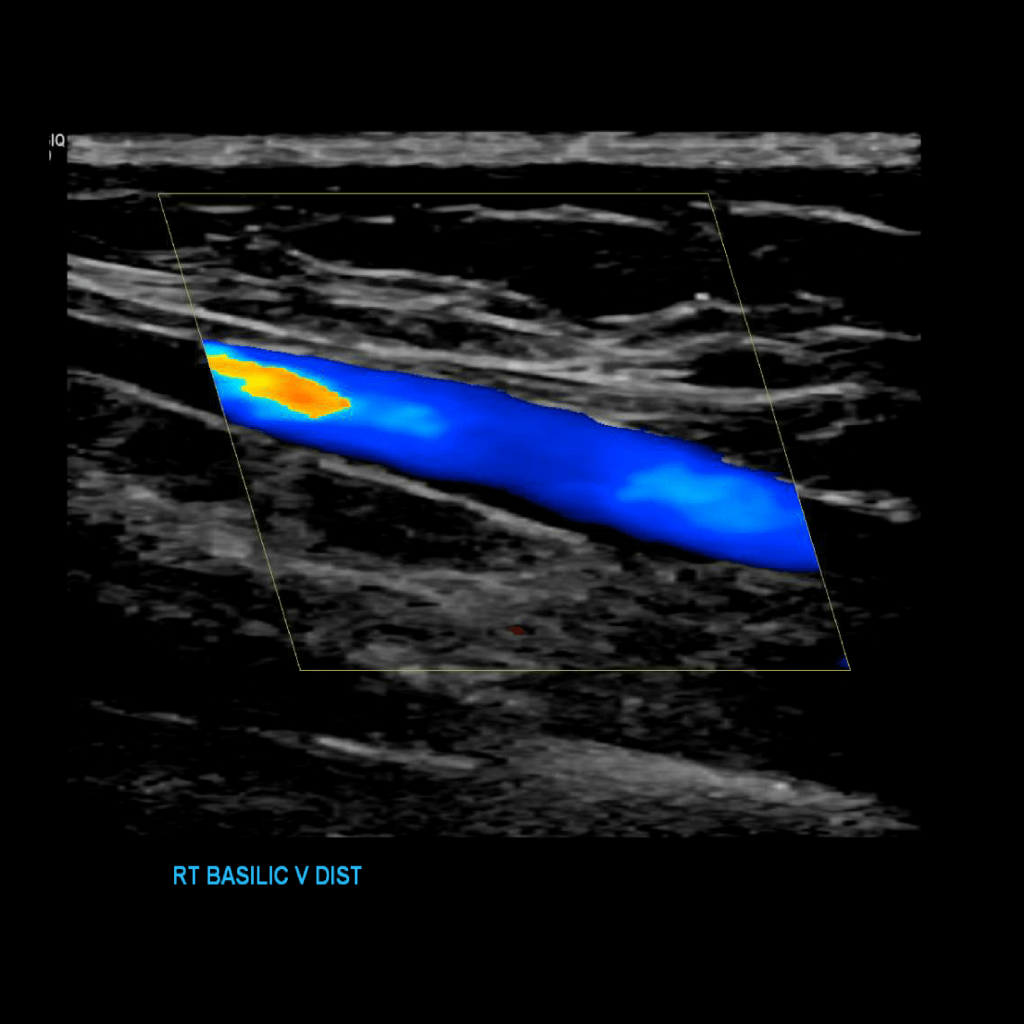

Scan the basilic vein in grey scale, compression, color doppler and spectral doppler

Thrombus of the right basilic vein